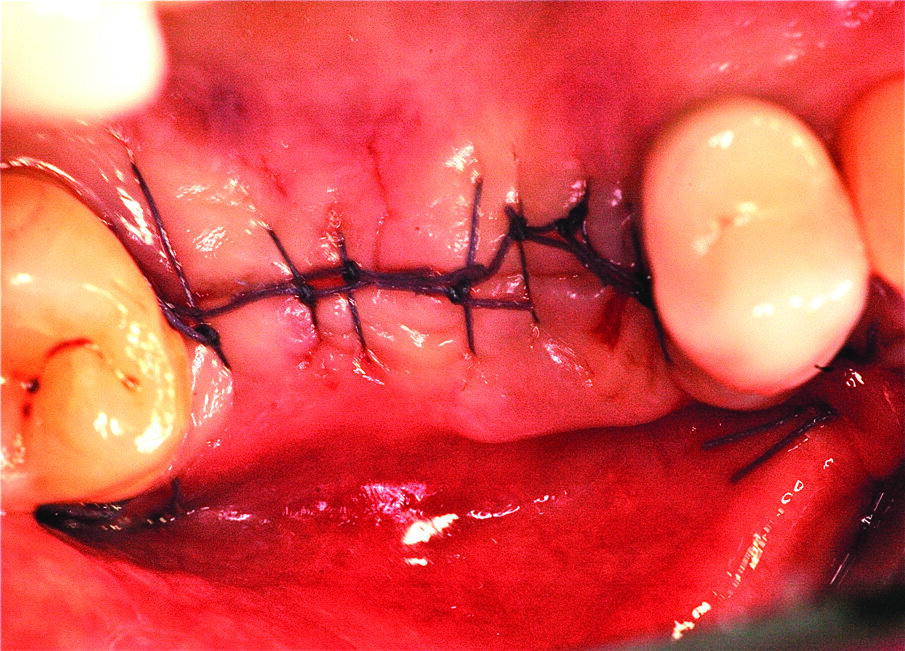

Una volta eseguito il disegno dell’antrostomia (Fig. 5), si procede al sollevamento della membrana con tecnica manuale (Figg. 6, 7) e all’iniziale inserimento di biomateriale granulare 0,5-1 mm (AlphaBio’s Graft, Alpha-Bio Tec, Israele). La corticale viene lasciata integra e aderente alla mucosa schneideriana in modo da diventare il futuro pavimento dell’antro (Fig. 8), anche per supportare il collasso della membrana durante il periodo di guarigione. A protezione della stessa è inserita una spugnetta di collagene equino (Condress, Smith&Nephew, UK). Contestualmente si procede con l’inserimento di due impianti autofilettanti SPI 3.75 x 13 mm (Alpha-Bio Tec, Israele) (Figg. 9, 10) e, al termine, viene ultimato il riempimento con biomateriale (Fig. 11). L’antrostomia viene poi coperta con una membrana riassorbibile 15 x 20 (AlphaBio’s Graft, Alpha-Bio Tec, Israele) e il lembo viene passivato e suturato con due linee di sutura 5-0: una a materassaio orizzontale e l’altra con punti staccati (Vicryl, Ethicon, USA) (Fig. 12). La paziente viene dimessa con la seguente terapia farmacologica: amoxicillina cpr 1 gr (1 cpr ogni 12h per 6 giorni), Prednisone cpr 25 mg (2 cpr per due giorni a scalare) per il controllo dell’edema post-operatorio e sciacqui con clorexidina 0.2% dal giorno successivo (1 sciacquo al giorno per 15 gg). Le suture sono rimosse a 15 giorni e la paziente è inserita in un programma di recall a cinque settimane per gestire eventuali complicanze durante la maturazione dell’innesto. Viene eseguito il secondo tempo chirurgico dopo 6 mesi e, verificata l’avvenuta osteointegrazione degli impianti, vengono rilevate le impronte e il caso è finalizzato con due corone unite in metallo ceramica (Figg. 13-15). Al termine della riabilitazione, visto il buon mantenimento igienico, la paziente viene inserita in un programma di follow-up a sei mesi (Figg. 16, 17).

Fig. 12_Particolare della sutura.